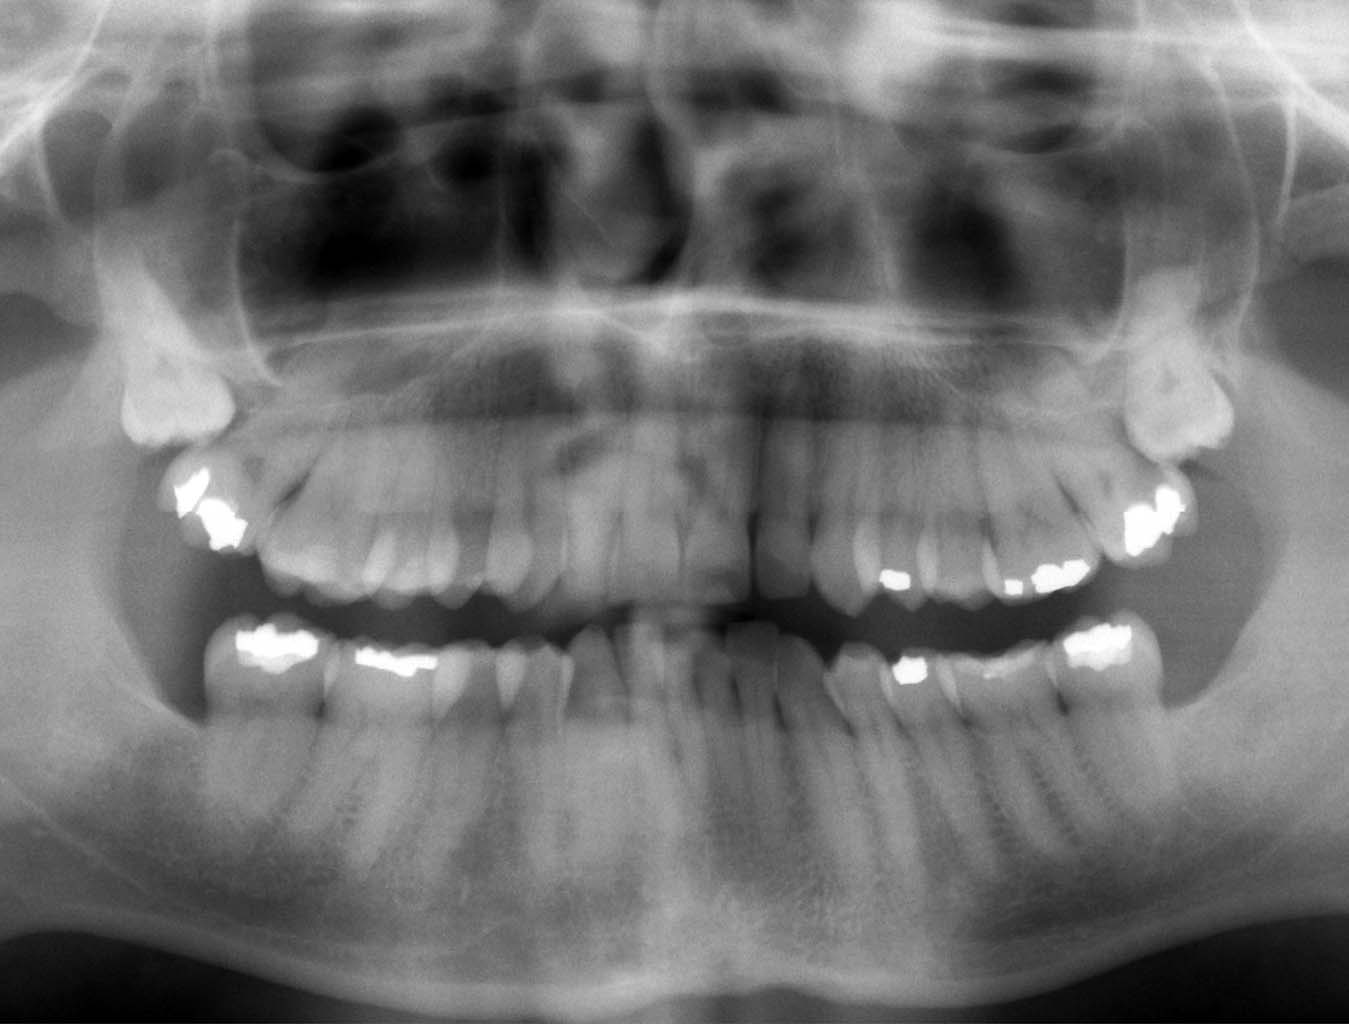

The dentist didn’t figure out what the problem was at first and ended up taking full 3D x-rays of my jaw in a cool machine. Diagnosis: My two remaining wisdom teeth are in a really strange position and a hole has formed between one of them and another tooth. Small pieces of food slip into the hole at the side of my tooth and infections can occur. The good news was that I had no cavities, the infection was gone and I got them to email me this cool picture which I can show you:

It looks kind of spooky, huh? Look at the strange placement of those wisdom teeth, to the upper far left and right, and how they press against my normal teeth. What a complete waste from the body’s point of view. Creating teeth is expensive. The energy and calcium could have been put to much needed use elsewhere. Bad genes.

The dentist advised me to get the wisdom teeth removed as soon as I got back to Norway and prescribed penicillin for me, in case I got another infection while on the road.